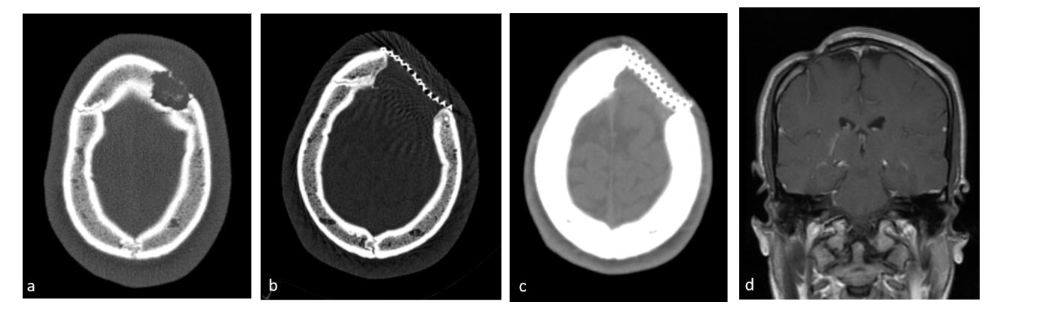

These procedures were performed under general anesthesia with intubation in the operating room. The lesion was removed and the surrounding abnormal bone tissue was sampled. During surgery, the neurosurgeon assessed for dural invasion. In earlier years a cranioplasty was performed as a second surgery and later on either cement or titanium mesh replaced the resected bone.

The median time between the biopsy request and procedure was 12 days (range 1–36 days). Surgical biopsy was diagnostic in all cases. Surgical interventions included resection in 24 cases and biopsy in 2 cases. Dural invasion was observed in only one instance. Bone replacement procedures were performed in 11 cases; one patient required a second operation for cranioplasty, 6 patients underwent cement replacement for skull defects, and 4 patients received mesh placement. Data were unavailable for 3 cases. The mean hospital stay following the procedure was 2.6 days (range 1–9 days), with 2 patients requiring intensive care on the first postoperative day.

Complications occurred in 14 patients (53.8%). Immediate postoperative complications occurred in 6 cases: three minor complications (two patients developed fluid collection at the site of resection, one with fever, another developed a hematoma at the surgical site) and three major complications (an infected titanium mesh, which was initially treated with antibiotics and later removed in a second operation, abscess at the surgical site, and a second surgery for completion of lesion resection in one patient). Late complications occurred in 8 cases and included headache in 2 patients, chronic sinusitis in one patient and esthetic cranial deformation in 5 patients. No anesthesia-related complications were reported.

In two FNB cases, on-site cytology yielded a diagnosis, facilitating rapid treatment initiation. These results are consistent with previous findings demonstrating the diagnostic value of on-site cytology in pediatric oncology. No complications occurred in the FNB group, whereas the surgical group experienced post-operative complications occurred in more than half of the patients (14/26), some major complications that necessitated a second surgery and prolonged hospitalization, and in 8 cases (30%) long standing complications including chronic headache, chronic sinusitis and in 5 cases deformation of the skull. The surgical group also exhibited a higher rate of bone defect repair, with titanium mesh and cement replacement being used in some cases. The current consensus recommends biopsy over resection for lesions larger than 5cm to avoid unnecessary enlargement of the bony defect and complications such as delayed healing or permanent skeletal deformities. For lesions between 2–5cm, biopsy combined with partial curettage is an acceptable option. Anesthesia-related complications were not reported in either group.